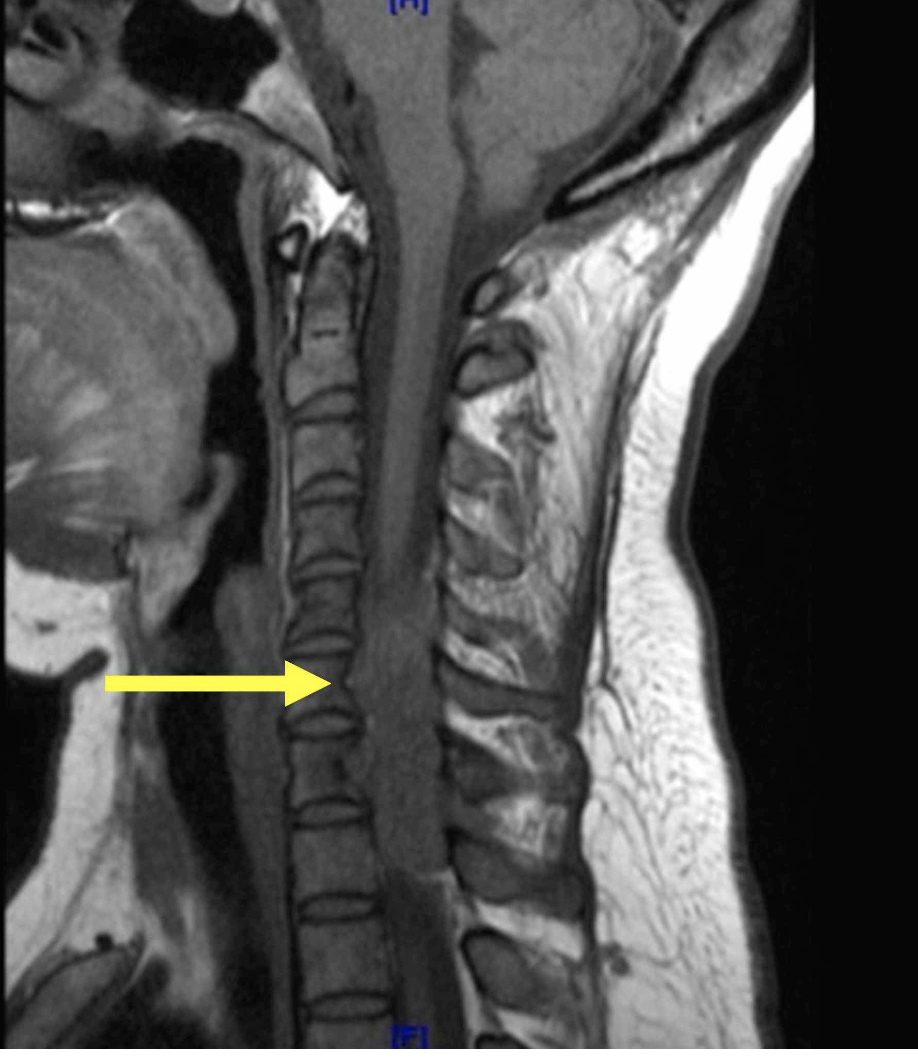

X-rays are generally performed on patients with suspected trauma of the spine. But which imaging technique would be classed as the gold standard for looking at the spine?

2 - MRI

• often identifies significant findings in asymptomatic patients requiring treatment

What is the main imaging of choice if you suspect a patient has spinal cord compression? 1 - X-ray 2 - CT 3 - MRI 4 - ultrasound

3 - MRI